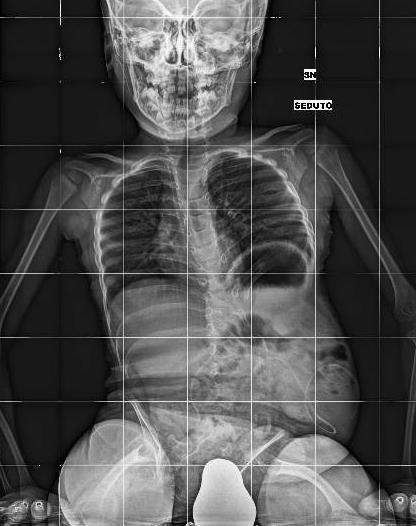

Lipomyelomeningocele, surgically treated at birth, neurogenic bladder and a previous epicystostomy for vescicoureteral reflux.

Left clubfoot treated with casting at birth. She underwent bladder augmentation and bladder neck reconstruction for urinary incontinence in 2016.

Male, 7 Yrs

Awaiting to taken in charge for rehabilitation treatment

Myelomeningocele surgically treated at birth. VP shunt.

Paraparesis. Bilateral neurogenic clubfoot, surgically treated. Hip dislocation